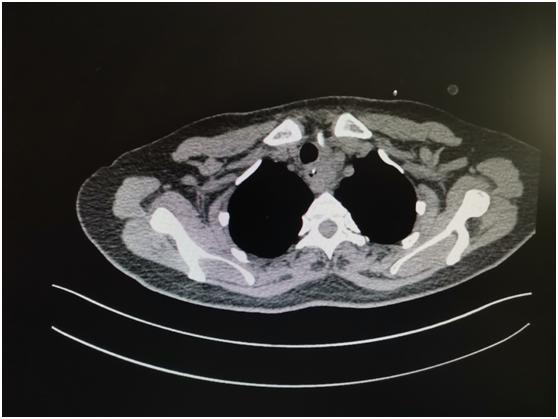

近日,患者来我院耳鼻喉科就诊,主任医师李学昌查看后嘱其立即行胸部 CT 平扫+强化,结果显示:食管上端见囊性影,大约 3.2 cm×4 cm,内见斜行条形高密度影及液气平面,增强见环形强化,此脓肿前位于气管后方,后至颈椎前方,上位于食管上端,锁骨水平,下至上纵膈。

李学昌、陈尧向患者及家属解释患者目前病情危急,感染加重随时可能出现纵膈感染甚至感染性休克,需要急诊手术取鸡骨,并解释手术方式及可能出现损伤喉返神经引起声嘶、损伤大动脉引起大出血等严重并发症,患者及家属表示理解,给予安排手术。手术由头颈外科手术经验丰富的陈尧主刀,于胸骨上窝一横指处颈部正中作横行切口,分离出左侧喉返神经,分离出甲状腺下级,分离出气管后壁、食管前壁,仍未发现脓肿,考虑可能位于食管后壁,继续探查食管周围,于食管后方发现脓肿,抽出约 15 ml 黄绿色脓液,臭鸡蛋味,于脓肿腔内发现约 2 cm 长鸡骨一块(如图)。冲洗脓腔,放置引流管,关闭术腔。